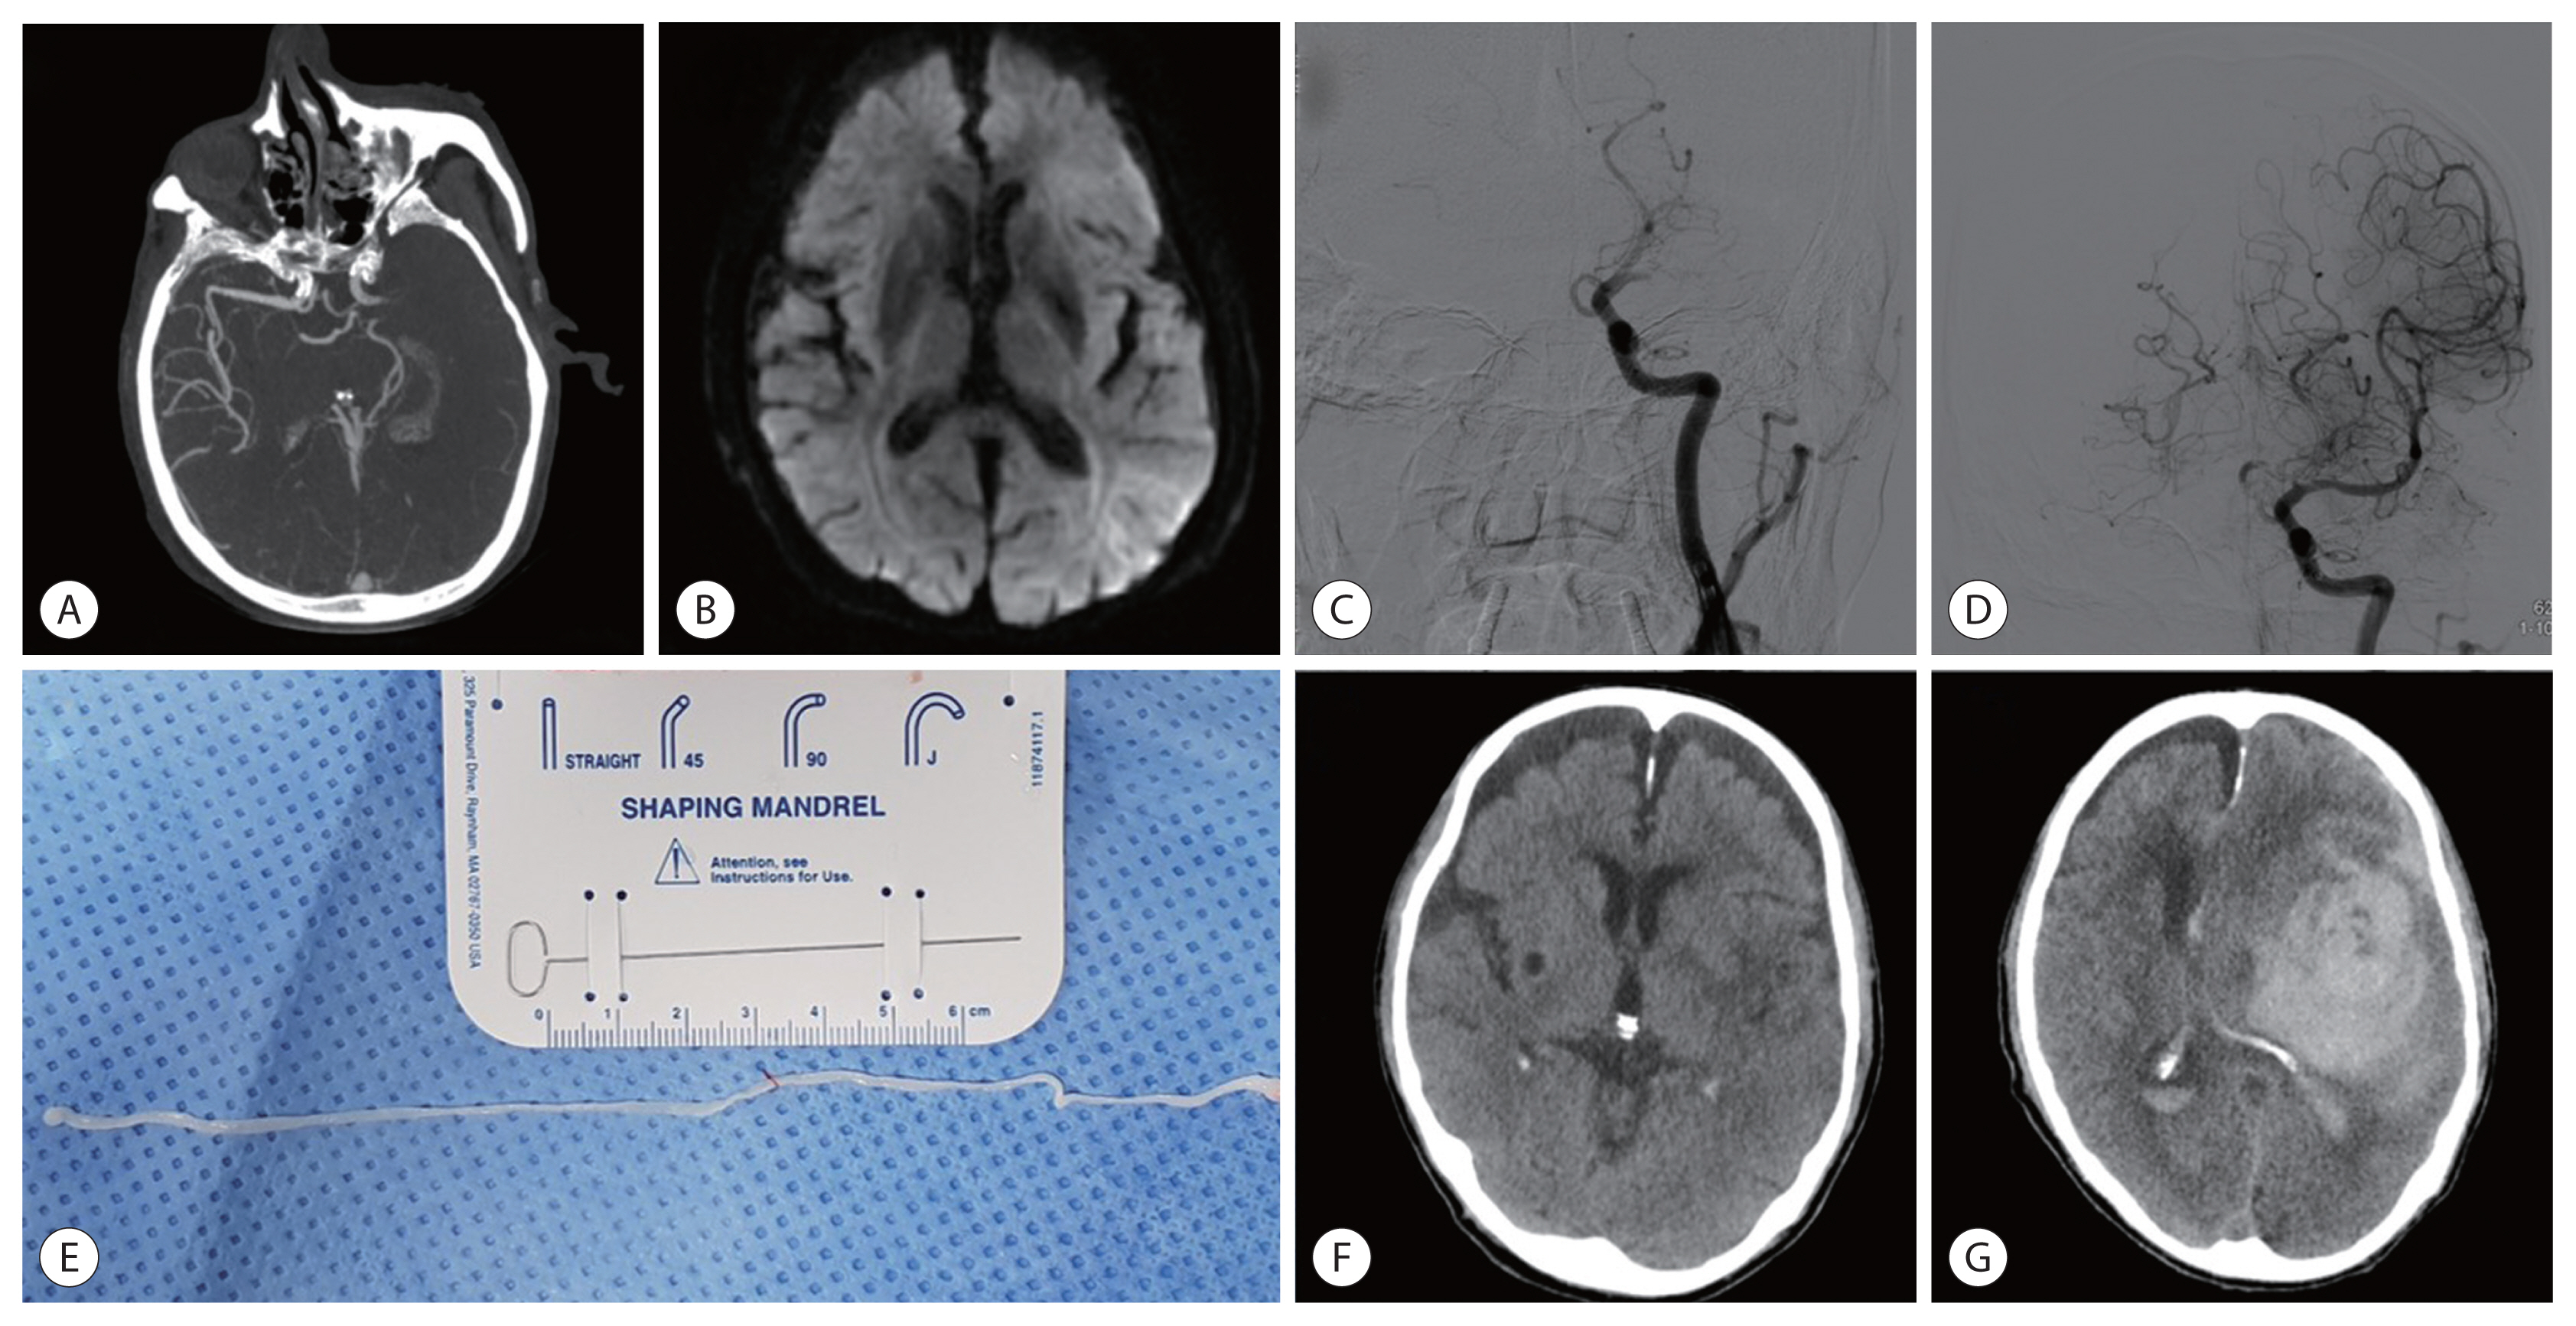

Initial brain computed tomography (CT) and supra-aortic CT angiography revealed subtle early ischemic changes on the left temporal area and acute occlusion of left middle cerebral artery (Fig. 1A). Subsequent diffusion-weighted imaging was performed to define the extent of ischemic lesions and to guide acute stroke therapies, which showed fuzzy hyperintensities on the left fronto-temporo-parietal area including left basal ganglia (Fig. 1B). Considering his clinical and imaging status, endovascular mechanical thrombectomy was performed to reperfuse the occluded vessel after 1.5 hr from symptom onset. Using contact aspiration and stent retriever techniques, partial reperfusion of occluded vessel was achieved (Fig. 1C, D). During mechanical thrombectomy, multiple fragmented whitish or reddish materials were retrieved from the occluded vessel. Among the retrieved materials, one whitish long segment material was mobile (Fig. 1E). To identify species, these retrieved materials were sent to the Department of Parasitology and Tropical medicine. At one day after index stroke, follow-up brain CT revealed hypodensities on left fronto-temporal area including left basal ganglia without any evidence of hemorrhagic conversions (Fig. 1F). During hospital stay, his neurological status was unchanged compared to baseline status despite the partial reperfusion of occluded vessels. At 15-days after index stroke, he suffered massive intracerebral hemorrhage on the affected hemisphere (Fig. 1G), and he died at the same day despite the medical management.

Fig. 1

Findings of an 89-year-old male with acute ischemic stroke. (A) Initial supra-aortic CT angiography showing acute occlusion of left middle cerebral artery. (B) Subsequent diffusion-weighted imaging at same day. (C) Initial left carotid angiography for endovascular mechanical thrombectomy. (D) Partial reperfusion of occluded artery was achieved. (E) One whitish long worm with sluggish movement. (F) Follow-up brain CT image at day 1. (G) After neurological worsening, a follow-up brain CT image showing massive parenchymal hematoma on the affected hemisphere.

Fig. 1 Findings of an 89-year-old male with acute ischemic stroke. (A) Initial supra-aortic CT angiography showing acute occlusion of left middle cerebral artery. (B) Subsequent diffusion-weighted imaging at same day. (C) Initial left carotid angiography for endovascular mechanical thrombectomy. (D) Partial reperfusion of occluded artery was achieved. (E) One whitish long worm with sluggish movement. (F) Follow-up brain CT image at day 1. (G) After neurological worsening, a follow-up brain CT image showing massive parenchymal hematoma on the affected hemisphere.